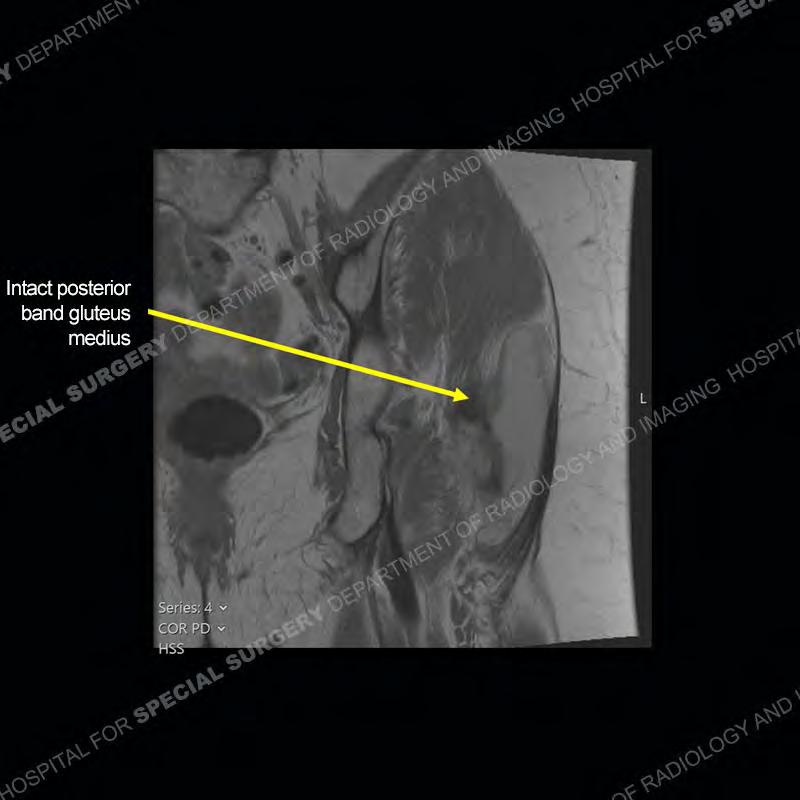

Not as much of a diagnostic dilemma as many of the other cases shown but just a nice example of the pathology seen of the gluteal tendons and a cause of trochanteric pain. Although, frequently thought of in isolation, trochanteric bursitis or bursal thickening is much more commonly a reactive change to underlying pathology of the subjacent gluteal tendons. The gluteus medius is divided into a posterior band and an anterolateral band. Tendinosis and partial tearing very commonly will involve the gluteus minimus and especially the more posterior fibers and then propagate into the anterior lateral band of the gluteus medius. Involvement of the posterior band of the medius is much less common and engenders a marked degree of functional impairment.